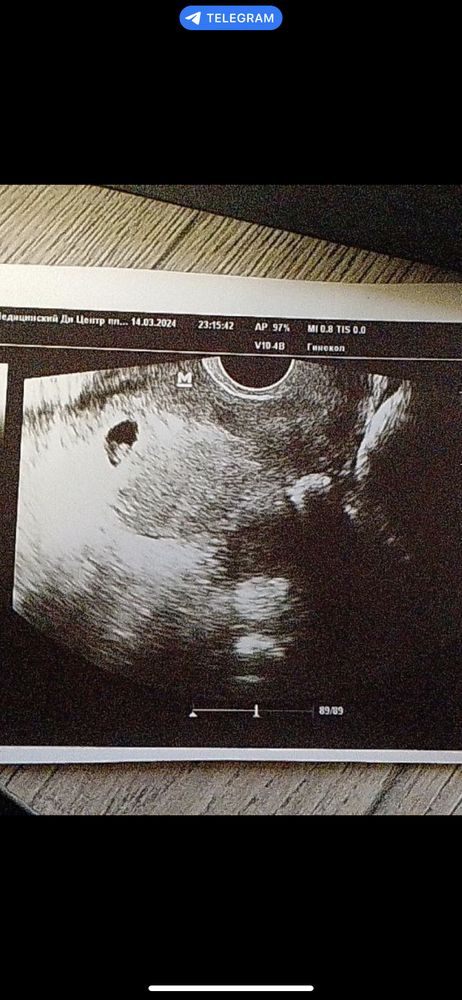

Маленькое плодное яйцо

По месячным срок 6.4, по узи 5-6 недель. Плодное яйцо 8мм. Сердцебиения не обнаружено. Ничего не понимаю. Лежу на сохранении из за отслойки. В понедельник узи. Почему размеры не соответствуют? Врач-узи в коммерческой клинике о сказала , что маленькая полосочка, это зарождается эмбрион. В больнице ничего не рассказали, не показали.

У меня после 13мм только нашли эмбриона в последний раз, рановато Вам пока) недельку можно подождать